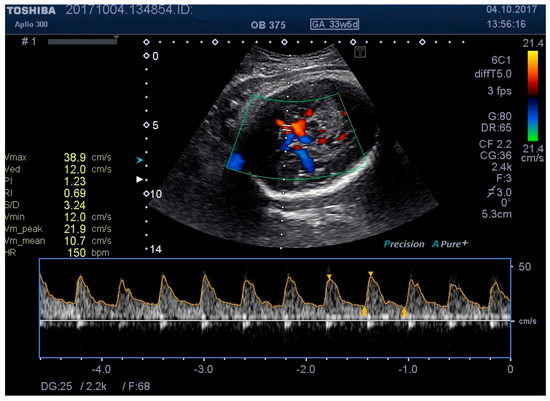

Figure 7. MCA Doppler spectrum with level 3 pressure.

Medicina 55 00410 g007

We examined the patients by transabdominal US, evaluating fetal lie and presentation, amniotic fluid index (AFI), area of placental insertion, and the abdominal wall thickness (AWT) including skin, subcutaneous tissue, and muscular wall. As a second step, we have evaluated the fetal cerebral vascularization, referring to the circle of Willis, with the help of color Doppler US, demonstrating the fetal MCA and recording the distance between the probe and the targeted vessel (e.g., MCA). By using pulsed Doppler examination, we recorded the flow velocity waveforms in the MCA, and measured the RI, PI, and PSV (using the highest point of the waveform). At the same time, we recorded, in a blinded manner, the applied pressure on to the maternal abdominal wall, considering this as a baseline pressure—needed for a proper evaluation of MCA. We then repeated the same measurements at two different higher pressure levels, while at the same time having a proper image of the targeted vessel. For the study methodology, we noted these pressure levels as level 2 and level 3.

Figure 1, Figure 2, Figure 3, Figure 4, Figure 5, Figure 6 and Figure 7 and Table 3 show the differences between MCA RI, PI, and PSV measured in the studied group, applying three different levels of abdominal pressure. As shown in the subsequent tables and figures, there are significant differences for the PI and RI levels with increase in abdominal pressure (median PI 1.46, 1.58, and 1.92, respectively; median RI 0.74, 0.78, and 0.85, respectively). Data are not following the normal distribution, thus, we used a Kruskal–Wallis test, which confirmed p < 0.05, for both PI and RI. At the same time, we found no significant differences for PSV in the studied group in relation to the increase in abdominal pressure (median PSV 39.56, 40.10, and 39.70 respectively). Data are not following the normal distribution, thus, we used a Kruskal–Wallis test, which showed p > 0.05.